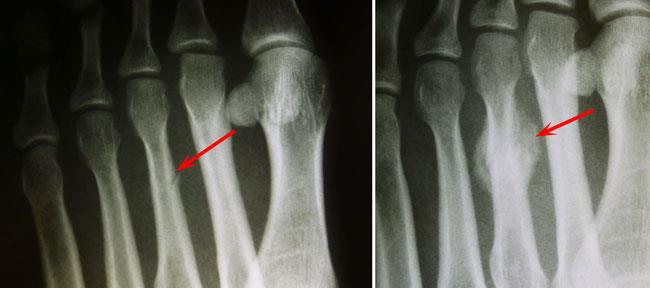

Stress fracture of third metatarsal

(Left) In this X-ray, a recent stress fracture in the third metatarsal is barely visible (arrow). (Right) Several weeks later, there is callus formation at the site and the fracture can be seen more clearly.

Images courtesy of Stuart J. Fischer, MD, FAAOS